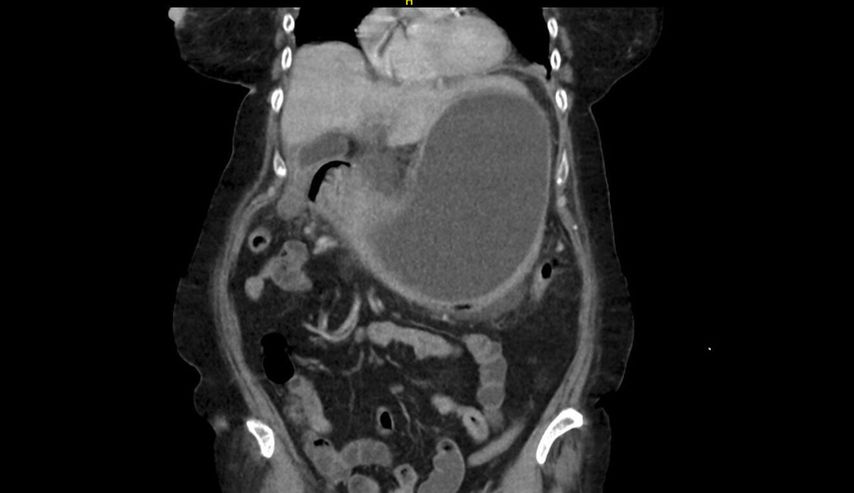

Es folgen eine sonografisch gezielte Punktion und perkutane Pigtail-Drainageanlage in die Fluidokollektion (Abb.3). Prompt entleeren sich 2,8l Pus. Die Drainage wird regelmäßig gespült und für 10 Tage belassen. In der Kultur des Punktats können Streptococcus anginosus und Klebsiella pneumoniae nachgewiesen werden, die initial eingeleitete Antibiose mit Piperacillin/Tazobactam wird antibiogrammgerecht umgestellt. Eine Kontrollgastroskopie (Abb.4) zeigt einen unauffälligen Befund am Pylorus und im Bulbus sowie in der Pars descendens duodeni, zahlreiche Biopsien der Magenschleimhaut ergeben eine geringgradige chronische, inaktive Corpusgastritis mit mukosalem Ödem.